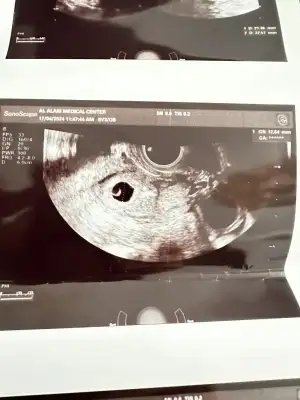

Ben 6.haftada hamile olduğumu öğrendim. Beta hcg 19.000 bindi. Hemen doktora gittik, keseyi gördük. 9 mmdi.

6+6 da kontrole gittim kese 25 mm olmuş. Hcg değerim de 37.000 olmuş. Ama bebek ve kalp atışı yok. Ultrasonda kese fotoğraftaki gibi gorunuyor.

Kesede ufak bir şey gorunuyor ama doktor bişey demedi. Haftaya tekrar bakacağız dedi. Sizce burada bir şey var mı? Benimle benzer durumu yaşayıp bebeği sonra gören var mı? Boş gebelik olmasından dolayı endişe duydum. Hcg değerlerim normal mi?, Hani Öncelikle geçmiş olsun Ben de aynı durumdayım ama ben doktora gitmedim işte bu ayın değil de diğer ayın 7'sinde randevu aldım gideceğim Evde beklemeyi tercih ettim Bir de bir şey soracağım peki Yani bir belirti var mı lekelenme işte karnında kıpırtı falan var mı